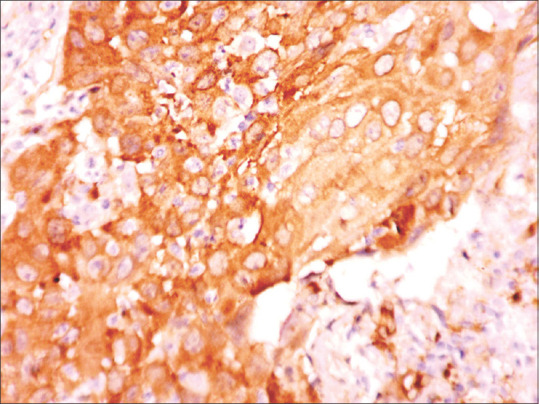

Materials and methods: A cohort study was conducted in the Department of Oral Pathology, SPDC, Wardha. A 4 μm thick section from paraffin-embedded blocks of formalin-fixed biopsy tissues of 60 cases having primary oral squamous cell carcinoma was processed and stained with mouse monoclonal fascin-1 (Clone: SPM133) antibodies.

Results: In the present study, all cases which had a final score above 2, denotes a strong positive immunostaining of fascin in OSCC. Tumour size was significantly correlated with fascin expression, whereas no significant association was found for other parameters, such as age, gender, node involvement, and grade of the tumour and recurrence.

Abstract Image